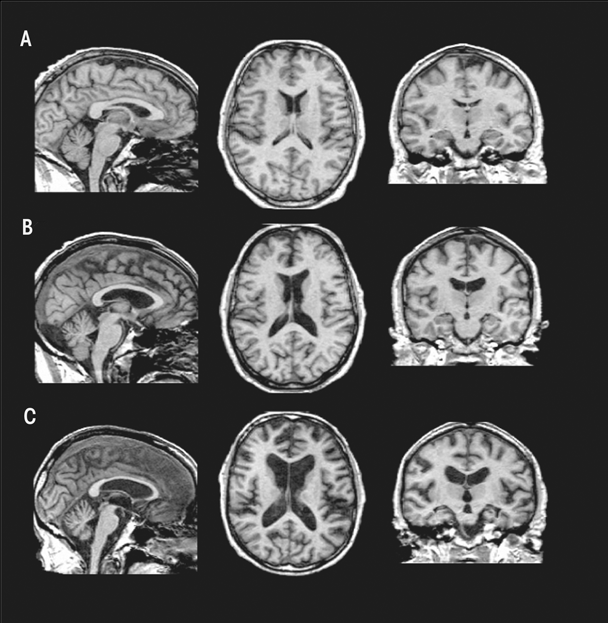

Structural MRI Findings in Uncomplicated Alcoholism

Relative to findings in WKS, research demonstrates mild volume deficits in the mammillary bodies (Shear et al. 1996; Sullivan et al. 1999), hippocampi, and thalami in uncomplicated alcoholics compared with healthy controls (De Bellis et al. 2005; Chanraud et al. 2007; Pitel et al. 2012; Sullivan 2003; van Holst et al. 2012). As shown in figure 5, these structures show a graded effect of volume deficits. That is, volume deficits are greatest in brains of subjects with KS (figure 5C) compared with brains of subjects with uncomplicated alcoholism (figure 5B) and brains unaffected by alcohol (figure 5A). Results suggest that mammillary-body damage is not prerequisite for the development of amnesia in alcoholism (Shear et al. 1996). MR findings also show hippocampal volume deficits in alcoholics compared with healthy controls (Agartz et al. 1999; Beresford et al. 2006; Kurth et al. 2004; Laakso et al. 2000; Sullivan et al. 1995; Wilhelm et al. 2008). Hippocampal volume deficits in alcoholism are influenced by age (Sullivan et al. 1995), even though age-related decline is difficult to detect in cross-sectional studies (Pfefferbaum et al. 2013; Raz et al. 2010; Sullivan et al. 2005b). Although deficits in hippocampal volume are not related to seizure incidence (Bleich et al. 2003; Sullivan et al. 1996), temporal-lobe white matter may be sensitive to alcohol-withdrawal seizures (Sullivan et al. 1996). Hippocampal volume shrinkage in alcoholism is attributed to loss of white matter and decreased axonal diameter (Harding et al. 1997). Glial cell loss (Korbo 1999) or reduced incorporation of newly formed neurons to the dentate gyrus (He et al. 2005; Nixon and Crews 2004), however, could also affect hippocampal volume in alcoholis